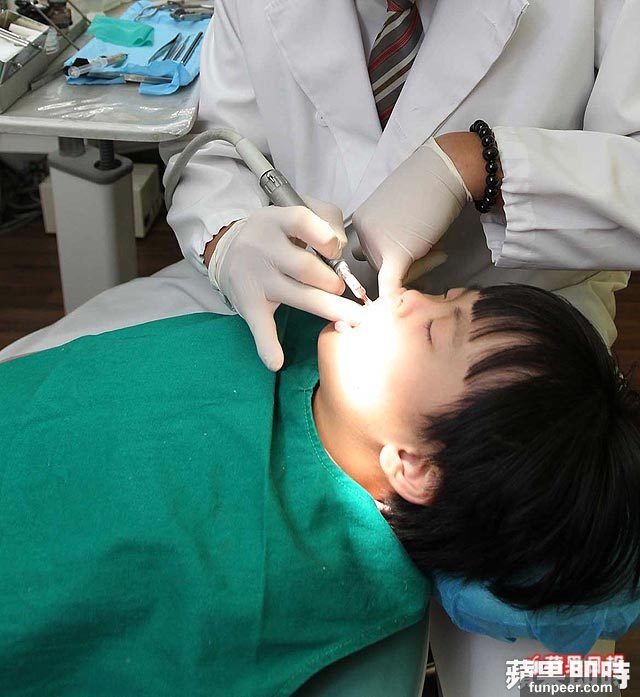

國外最新技術宣布「無痛生出一顆牙齒」!醫療團隊透露:「只要九個禮拜」...怕看牙醫的人有福了!

你也是害怕看牙醫的人嗎?如果很不幸地,牙齒已經蛀掉了,又沒辦法長出新的,蠻多人會選擇植牙或是裝假牙!不過國外一項發明卻指出,缺牙齒的人有福了!因為現在最新技術已經做到:只要九個禮拜... 圖片來源:Appledaily

圖片來源:Appledaily一般缺牙齒的人,都會選擇植牙,植牙的原理是,用人工牙根安裝假牙、彌補缺齒,可以提供像是自然牙齒的咬合力,而且舒適性、美觀都比傳統假牙好,只要患者注意口腔衛生、定期接受檢查,是可以長期使用的!

圖片來源:Appledaily不過,植牙確實也有風險存在,像是傷口感染、腫脹出血、癒合不良等等,很有可能不如預期,而必須再次手術治療!因此,美國哥倫比亞大學醫學中心的「傑里米」博士(Dr.Jeremy Mao),最近就發表了一項破天荒的技術...